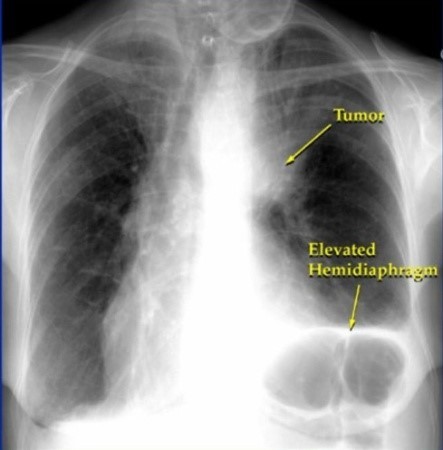

- 정기적인 건강 검진: 위와 같은 증상이 하나라도 나타나면 즉시 병원을 방문하여 흉부 X-ray, CT 촬영 등 검사를 받는 것이 중요합니다.